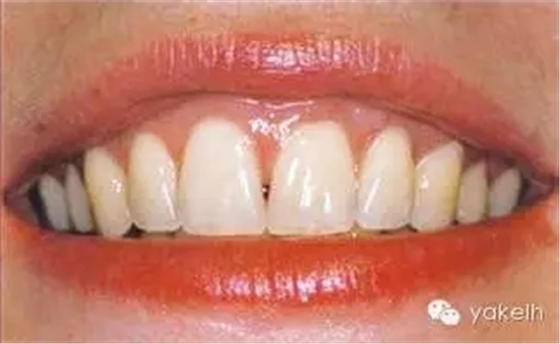

圖5.11 (a)患者休息放松狀態(tài)下的嘴唇——上下唇不能完全閉合。(b)右上尖牙和側(cè)切牙呈Ⅰ類牙齦退縮。(c)左上頜尖牙和側(cè)切牙呈Ⅱ類牙齦退縮。(d)先用圓形眼科刀片開始做溝內(nèi)切口。(e)使用探針在袋內(nèi)垂直探查貫通隧道,越過膜齦聯(lián)合。(f)使用探針在隧道內(nèi)橫向探查貫通,保留齦乳頭尖端附著于骨面。(g)從腭部取結(jié)締組織移植物,使用絲線牽引,將厚度和大小足夠的結(jié)締組織瓣插入隧道內(nèi)。(h)通過懸吊縫合將組織瓣冠向復(fù)位,穩(wěn)定結(jié)締組織瓣。(i)術(shù)后6個(gè)月,上頜右側(cè)觀。(j)上頜左側(cè)觀,可見牙齦厚度以及色澤的協(xié)調(diào)性均得到改善。(k)術(shù)后6個(gè)月正面觀,牙敏感癥狀消失。(l)術(shù)后1年的全口影像,顯示雙側(cè)的牙齦退縮均被完全覆蓋,牙齦邊緣增厚且穩(wěn)定,與釉牙骨質(zhì)界輪廓一致,也與左側(cè)中切牙釉質(zhì)缺損輪廓一致。(m)患者嶄新的笑容,可見側(cè)切牙及尖牙的齦緣無退縮。